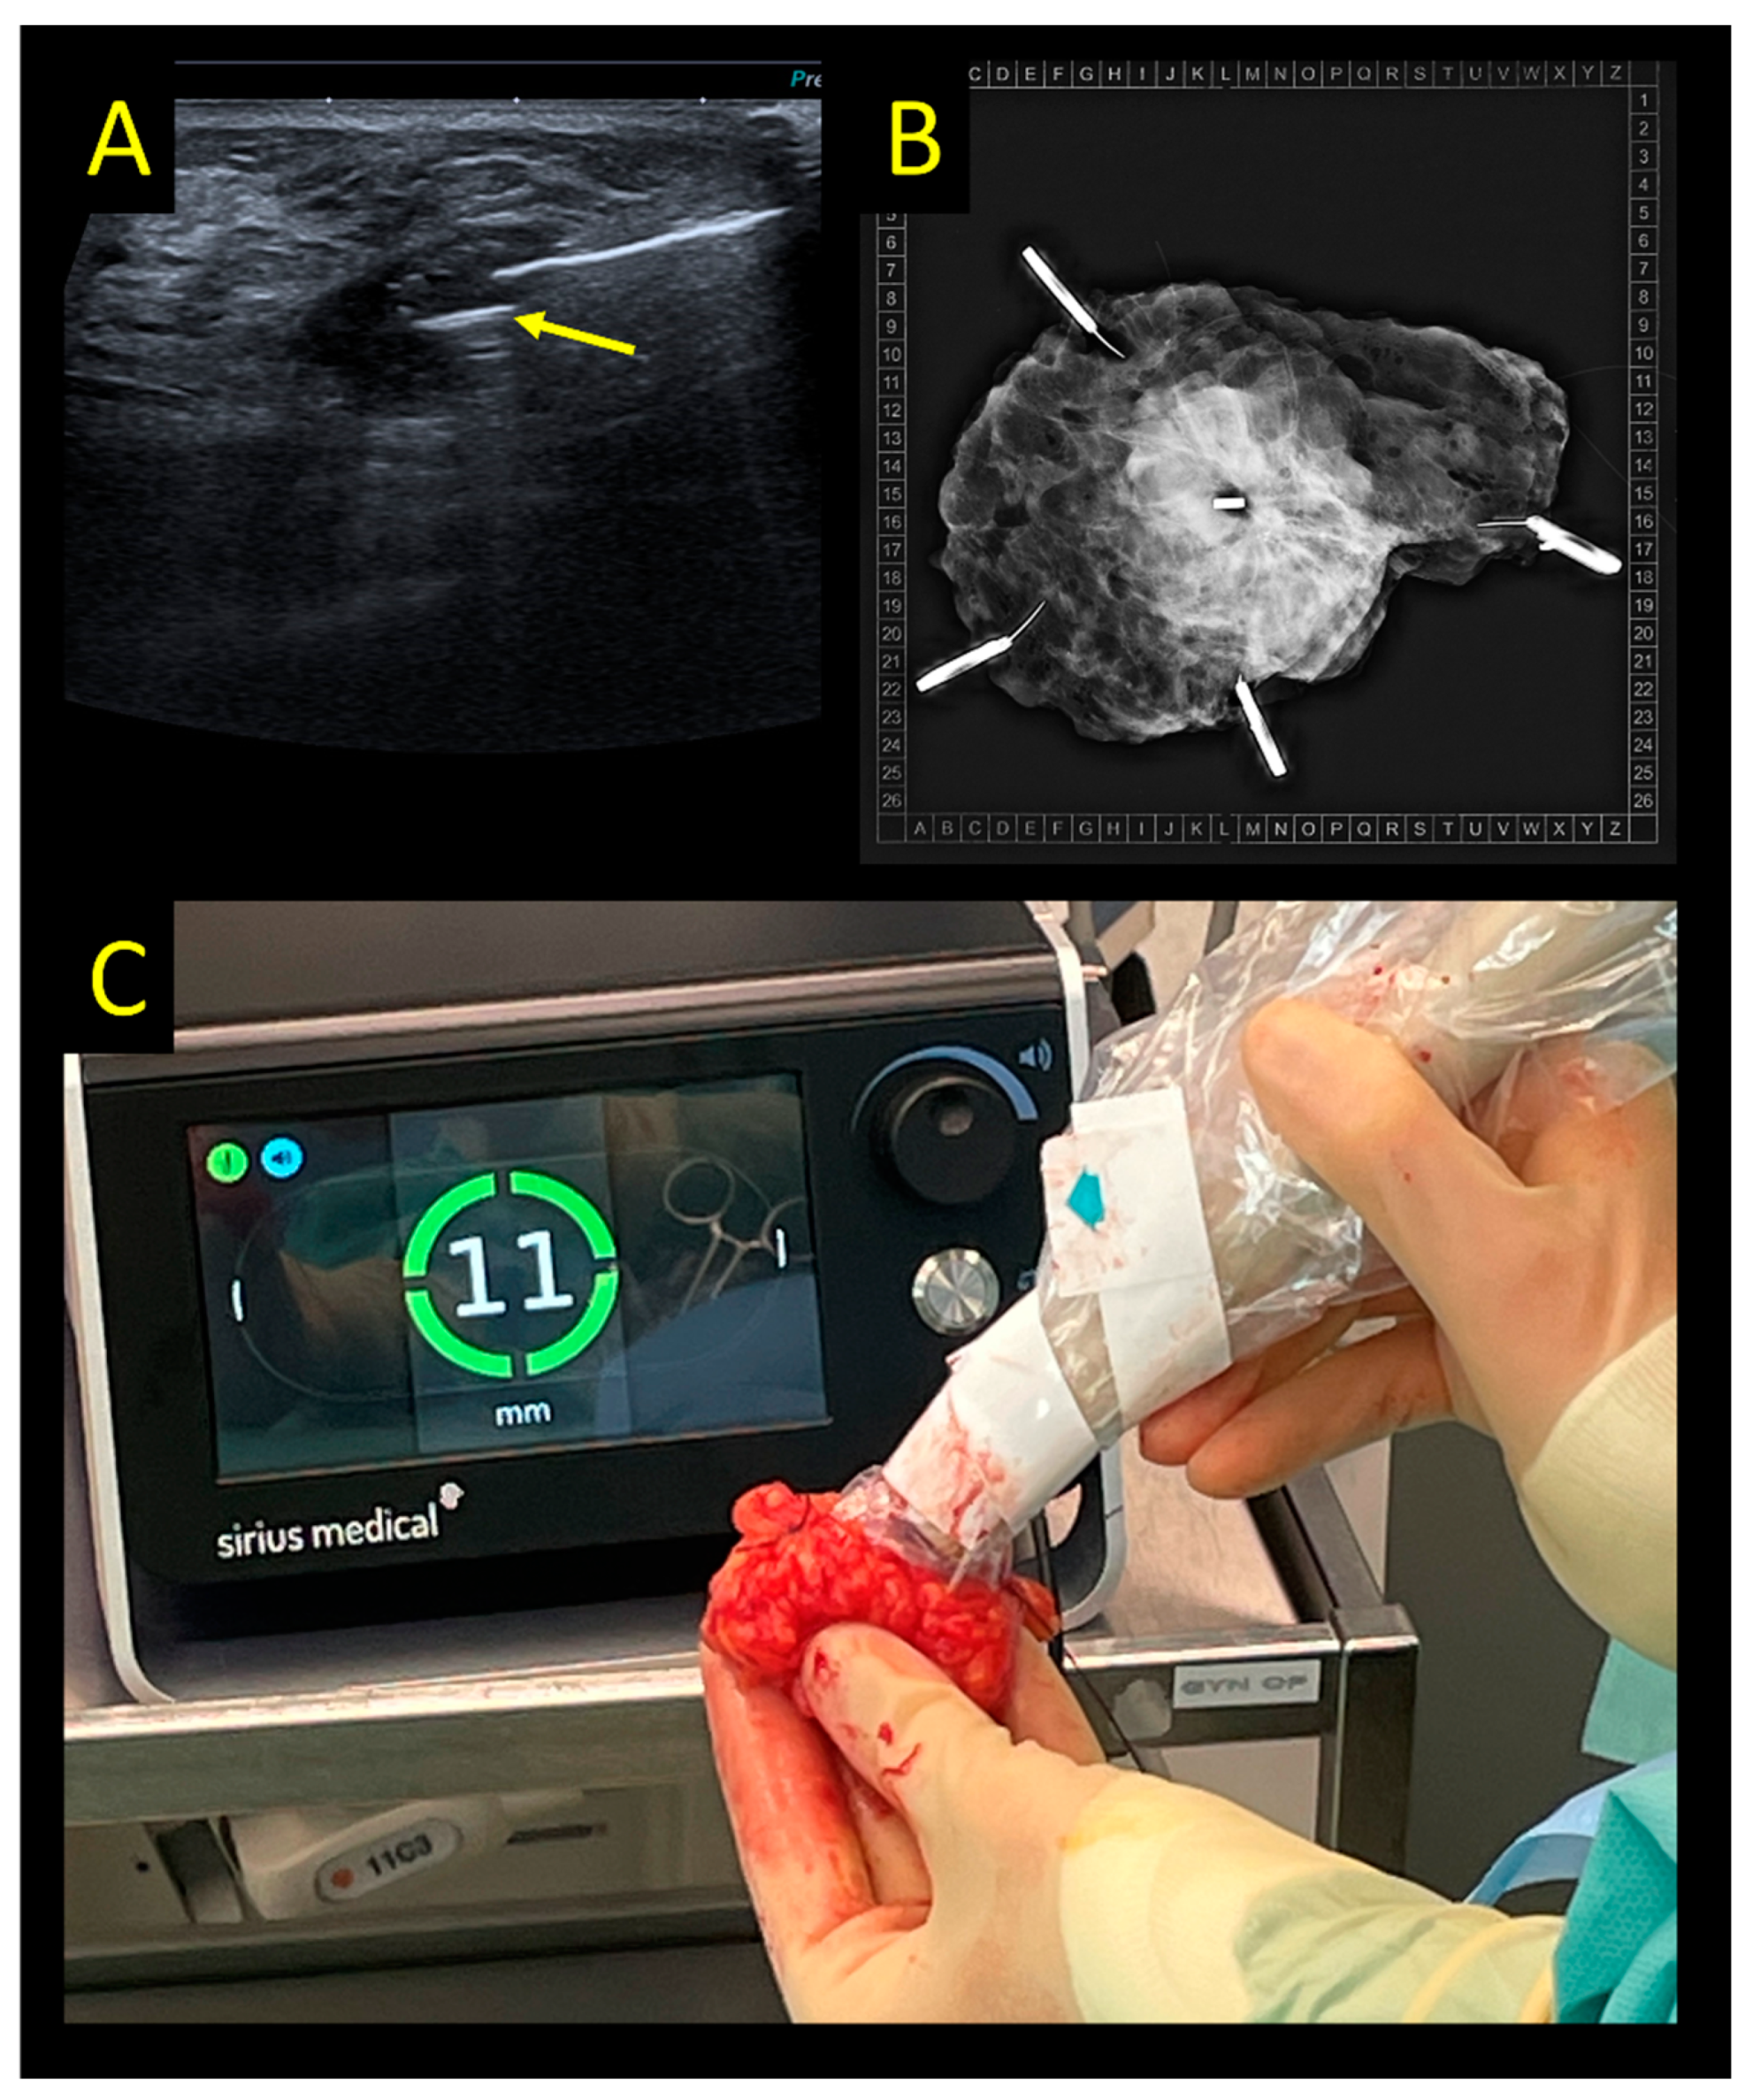

2.7. Intraoperative Ultrasound

- Banys-Paluchowski, M.; Paluchowski, P.; Krawczyk, N. Twinkle artifact in sonographic breast clip visualization. Arch. Gynecol. Obstet. 2022. [Google Scholar] [CrossRef]